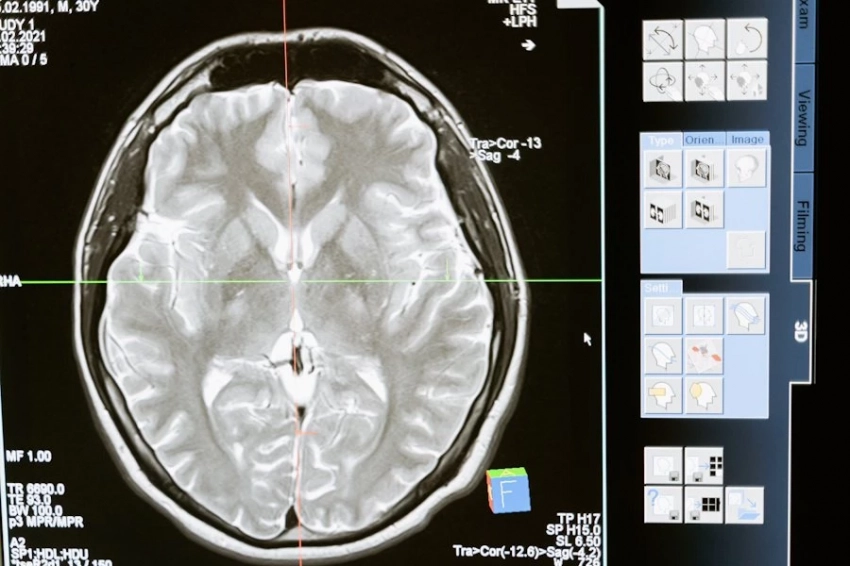

Исследователи из Пенсильванского университета сделали значительный шаг вперед в борьбе с одной из наиболее агрессивных форм опухолей мозга — глиобластомой. Они представили новую методику, основанную на усовершенствованной технологии CAR-T терапии, которая нацеливается сразу на два опухолевых антигена — EGFR и IL13Rα2. Это нововведение позволяет значительно повысить точность и эффективность воздействия на злокачественные клетки, что является критически важным в лечении такой сложной болезни.

Одним из ключевых отличий новой методики является способ введения модифицированных иммунных клеток. В отличие от традиционных подходов, клетки доставляются непосредственно в спинномозговую жидкость, что обеспечивает более тесный контакт с опухолью и, как следствие, улучшает результаты лечения. Это обстоятельство подчеркивает значимость прямого взаимодействия терапевтических агентов с опухолевыми клетками, что может существенно повысить шансы на успех.

Результаты клинических испытаний, в которых приняли участие 18 пациентов с рецидивирующей формой глиобластомы, оказались обнадеживающими. Учитывая, что стандартная выживаемость таких пациентов составляет менее года, результаты испытаний показали, что у 62% участников наблюдалось уменьшение объема опухоли. В группе из семи тщательно отслеживаемых пациентов 43% смогли прожить более года, что значительно превышает средние показатели выживаемости.